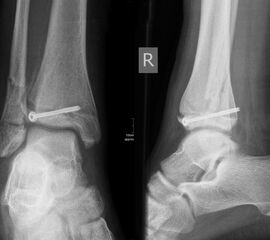

THERAPIE

Behandlungsziel ist die exakte Rekonstruktion der Gelenkfläche sowie die Minimierung des Risikos einer späteren Wachstumsstörung. Dislozierte Frakturen werden offen reponiert, die Osteosynthese erfolgt mit einer Kleinfragmentschraube. Finden sich viele kleine Fragmente kann eine K-Draht Osteosynthese durchgeführt werden. Wird der Innenknöchel operiert, kann bei gleichzeitiger hochgradiger lateraler Instabilität eine Rekonstruktion des lateralen Bandapparats durchgeführt werden. Fibula Frakturen stellen sich meist spontan ein, sodass hier keine zusätzliche Osteosynthese notwendig ist.

Nach der Osteosynthese wird die Fraktur für ca. vier Wochen in einem Unterschenkelgips ruhiggestellt. Bei Schmerzfreiheit der Frakturzone erfolgt anschließend eine schmerzadaptierte Belastungssteigerung über weitere zwei Wochen. Sobald unter Alltagsbedingungen Beschwerdefreiheit besteht kann die sportliche Belastung langsam gesteigert werden. Kirschnerdrähte werden 6-8 Wochen postoperativ, Schrauben nach zwölf Wochen entfernt. Es empfiehlt sich klinische und radiologische Kontrollen im Abstand von 6 Monaten bis zum Wachstumsabschluss durchzuführen, um ein mögliches Fehlwachstum frühzeitig zu erkennen.